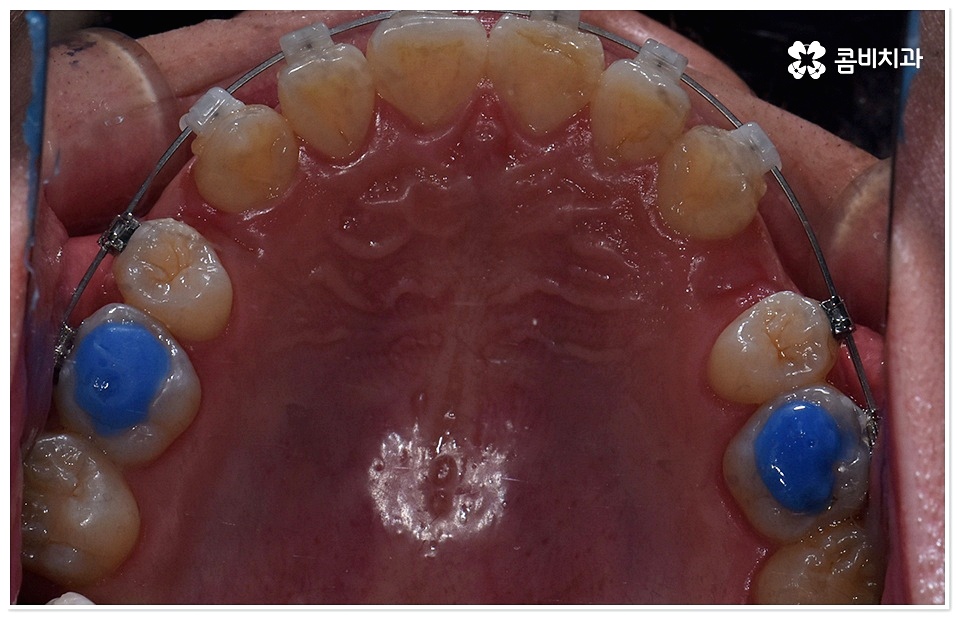

교정 치료란 특수한 장치를 이용해 치아를 원하는 방향으로 이동시켜 치아 배열과 교합을 올바르게 개선해 주는 과정으로 각자의 구강 구조가 다 다르기 때문에 정밀 검사를 통해 환자분들 각각의 치아 모양과 각도, 위치, 교합 뿐 아니라 잇몸 건강 상태 및 상악과 하악의 관계와 같은 구강 내 상황과 함께 입술, 전체 안모 등 대칭과 균형의 측면에서 모든 부분을 다각적이고 입체적으로 분석한 후 세밀한 맞춤 계획을 수립하는 것이 중요할 수 있는데요.

그러므로 3D CT와 같은 정밀 검진 장비와 3D 모르페우스와 같은 시스템을 갖추고 다양한 경험과 노하우를 바탕으로 정확한 진단 및 섬세한 플랜을 세울 수 있는 치과를 잘 알아보고 덧니치아교정 치료를 진행하실 필요가 있어요.